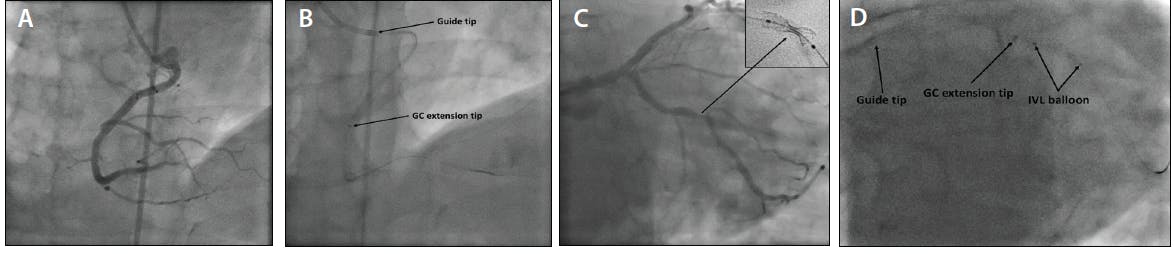

Figure 2. The low anterior origin right coronary artery (RCA) resulted in poor guide support, but deep GC extension intubation into the RCA provided enough support to cross the occluded posterior descending artery (A, B). An unexpanded stent in the second obtuse marginal branch (C). Deep intubation of a GC extension just proximal to the stent allowed delivery of an intravascular lithotripsy (IVL) balloon (D).